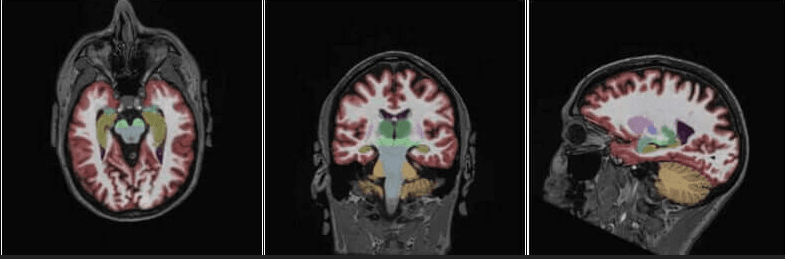

NeuroQuant is an AI-assisted program that compares your brain images to a normal population to determine volumetric changes as well as to show possible improvements from drug therapies or other forms of treatment.

The additional neuroquant sequences add no more than about 6 minutes to your exam, but they provide a wealth of information about your brain health. This program targets areas in the brain for:

Brain age/dementia/alzheimer's changes multiple sclerosis (changes, improvements) traumatic brain injury and the areas affected

Seizure/epileptic changes in the temporal lobes

Brain tumors and the areas of the brain affected by tumor, edema, radiation, etc.

Brain development in adolescents and developmentally-challenged adults covid-related changes

If you have a family history of dementia or alzheimer's or a personal history of any of the aforementioned anomalies, you qualify for the exam. Even if you are asymptomatic, this scan can provide baseline information, as future exams will be directly compared to your own NeuroQuant imaging studies to identify changes in your brain structure volume.